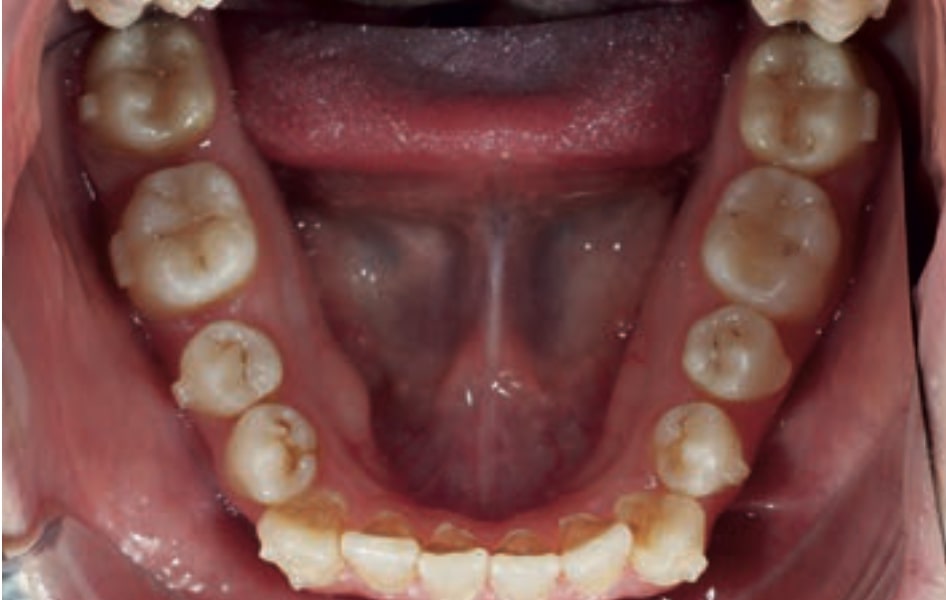

Chief complaint: The patient, a 19-year-old woman, was evaluated to undergo orthodontic treatment using the Angel Aligner Pro system. She presents with a skeletal Class III, mesofacial, with a dental Class III malocclusion and a 2 mm deviation of the lower midline to the left. Teeth 33 and 43 are out of the arch and cortical bone, with a crossbite issue on tooth 33. Fortunately, no functional issues affecting swallowing or breathing have been detected. The patient’s motivation for starting treatment was a general review of her dental and aesthetic health. The soft tissue analysis reveals mandibular protrusion that influences her facial profile. This diagnosis highlights the need for a comprehensive approach to address dental and skeletal misalignments, improving both the patient’s functionality and facial aesthetics.

- Dental Class III, 2 mm deviation of the lower midline to the left. 33 and 43 out of the arch and the cortical bone.

- Level Curve of Spee.

- Intrusion of the Lower Anterior Teeth: Adjust the vertical position of the lower anterior teeth to level the curve of Spee, improving the harmony of the occlusion.

- Improve the Root Position of Teeth 33 and 43: Optimize the position of the roots of teeth 33 and 43 in relation to the cortical bone to ensure adequate bone support and long-term stability.